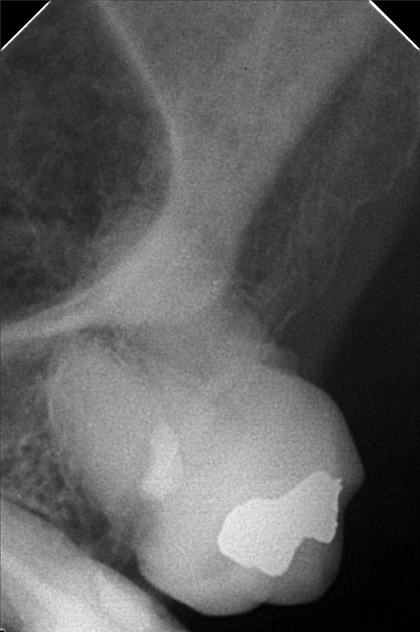

- 04/22/22 - check up/ for exo 26/ resto 21, 35, 15, 16, 17 cervical, cleaning with ozone ***under Iv sedation *** medical clearance 05/27/22 - Lc 21/34/35/ 15/ 16/ 17 exo 26 with suture and gel foam / Op with ozone 05/28/24 Xray OP 07/02/24 #24(2 canal) 1st RCT buccal canal 20mm 07/20/24 #24 buccal lingual 20mm (2nd RCT) 07/27/24 3rd RCT #24 20mm Caoh paste TF nxt obturation 08/03/24 #24 OBturate 09/04/25 LC #21 I #34 C W/ CAoH #35 O W/ CAoH XRAY 3D SCAN ALUMINA CROWN 22,24,25 BAL. 36,000 09/11/25 Install of Crown # 22,24.25